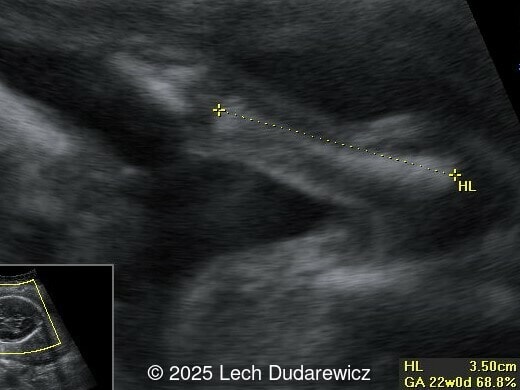

Ultrasound revealed a single live fetus with 46,XY karyotype. Biometric measurements demonstrated discrepancies with the femur and tibia length lagging significantly at 19 weeks and notable shortening and bowing of the femur, tibia, and fibula. The findings were consistent with skeletal dysplasia.

Prenatal ultrasound is a crucial tool for early diagnosis, enabling appropriate counseling and perinatal management of campomelic dysplasia. Key skeletal abnormalities include significant shortening and bowing of long bones, particularly the femur and tibia. In a study by Mansour et al, the lower extremities are primarily involved with minimal bowing of the humerus, ulna, and radius. Bowing often presents with associated angulation, giving rise to the term "campomelia," meaning bent limbs in Greek. Hypoplastic iliac bones and scapulae are hallmark features, while rib anomalies such as deformities or reduced number, typically 11 pairs, may also be observed. Additionally, the chest may be narrow and bell-shaped. Cervical spine abnormalities, including excessive lordosis or kyphosis, are often present and may contribute to postnatal respiratory complications. These findings are important for risk stratification and delivery planning.